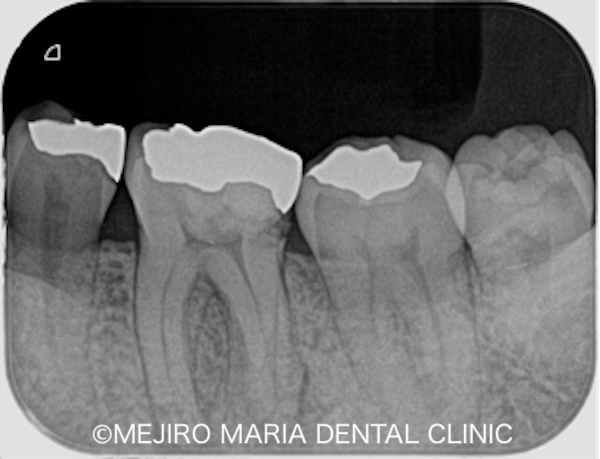

根管治療は2回で終了し、2回目の治療では長年歯茎に見られていたフィステル(瘻孔)も消失していました。症状の消失が確認できたため最終補綴処置に移行しました。今後3ヶ月間〜2年間の経過観察を行い、引き続きフォローアップする予定です。